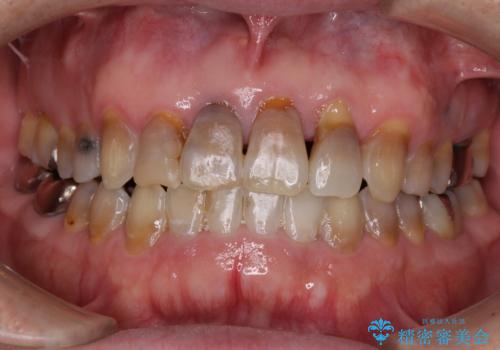

- 前歯の叢生と臼歯のクロスバイトを気にして来院された患者様です。

急速拡大装置による上顎の側方拡大を行い、その後はインビザラインより歯列を改善することとしました。

20代後半以降の男性は上顎骨の側方拡大処置の成功率が低く、今回も骨を拡大することができませんでした。

しかしながら、歯列を側方に拡大することができ、その後はインビザラインにて叢生を解消することができました。